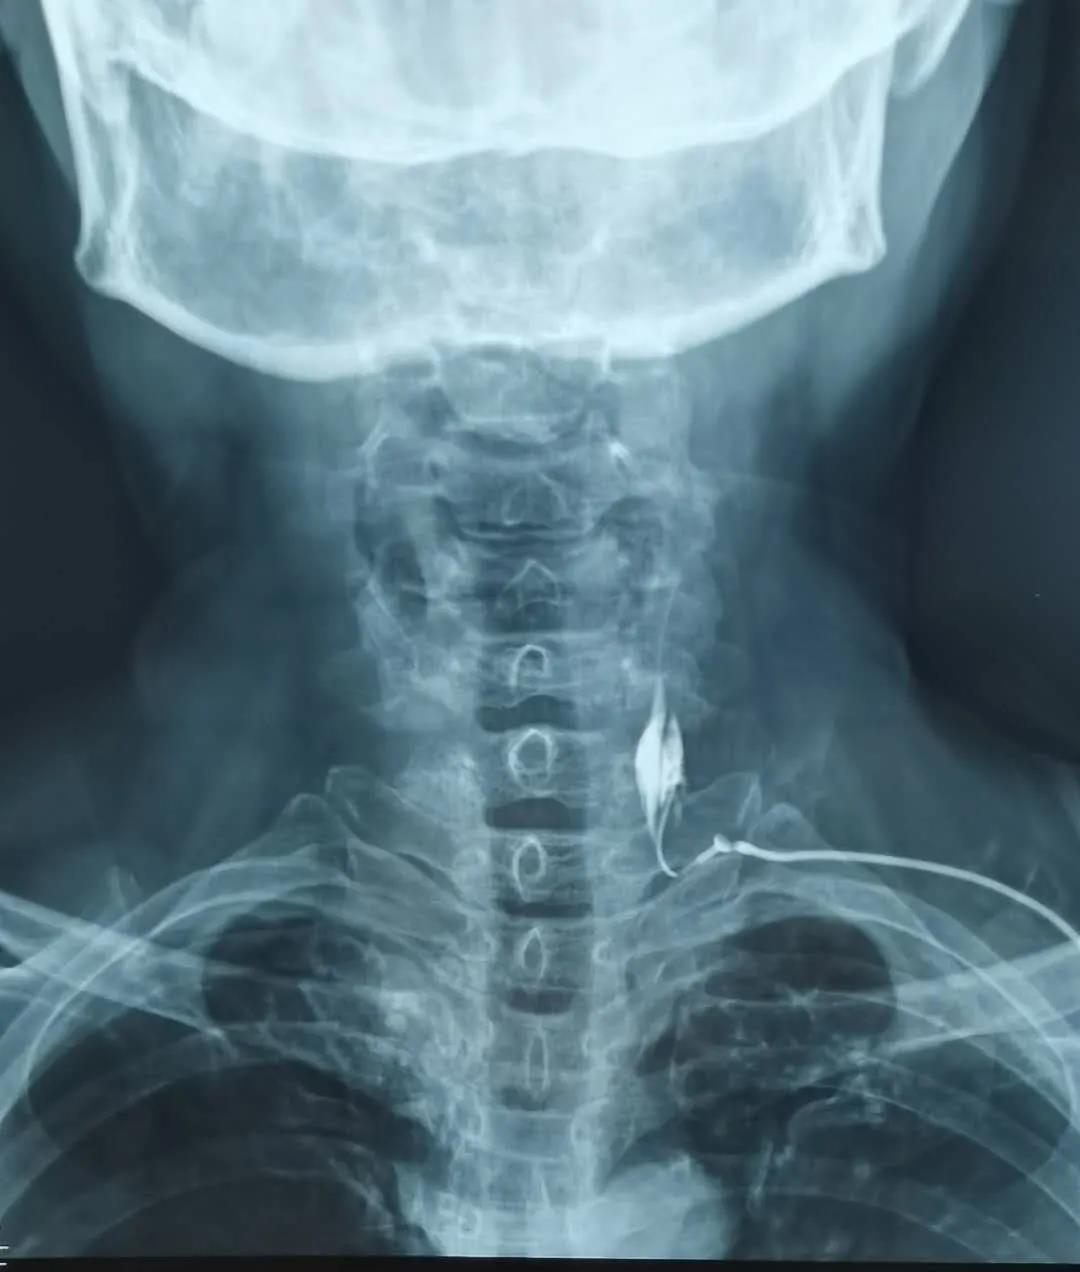

頸部星狀神經(jīng)節(jié)阻滯術

濰坊市市立醫(yī)院疼痛康復科、骨科在積極治療原發(fā)病的基礎上,采用正清風痛寧三連續(xù)貫療法,消炎去痛,改善微循環(huán);針刀松解等可以解除血管神經(jīng)等壓迫,改善組織供血和神經(jīng)功能;星狀神經(jīng)節(jié)阻滯術,調節(jié)人體的交感神經(jīng)和副交感神經(jīng)系統(tǒng),調節(jié)機體的產(chǎn)熱和皮膚散熱,維持機體和組織器官的溫度恒定。全身和局部治療結合,中西醫(yī)措施結合,對肢體寒涼等疾病的治療,互相補充,相得益彰。